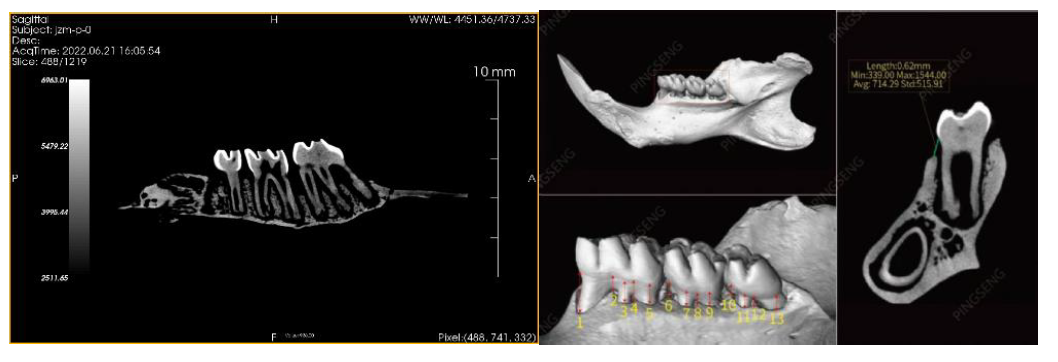

2、Micro -CT 在齿科研究中的应用,用以评价植入材料或药物对牙槽骨或口腔修复的效果